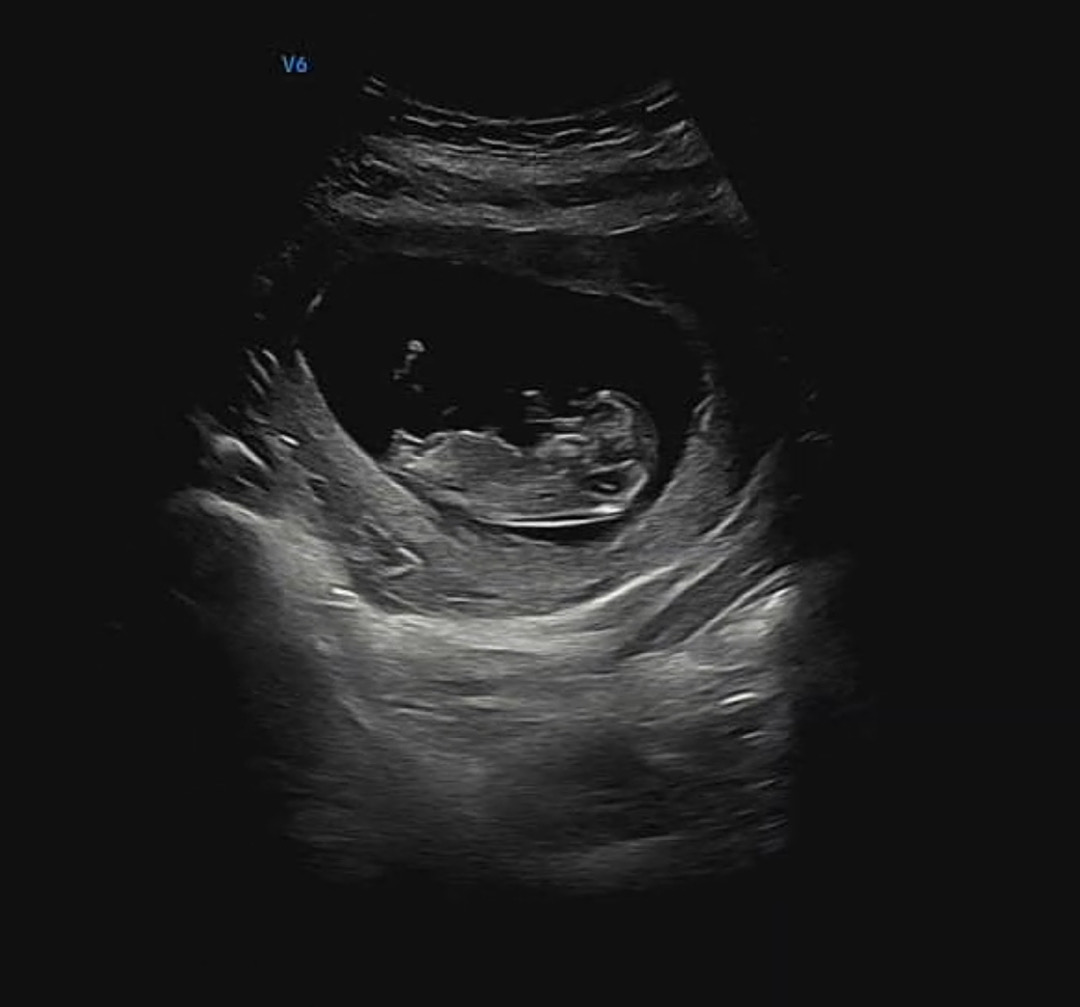

/ 성별질문

주변에서 5:5로 나뉘어서 각도법 고수님 찾아요